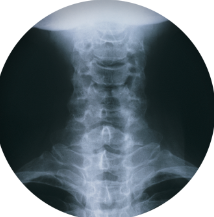

목디스크 증상 원인 치료방법 등 목디스크에 대한 정보를 알아보도록 하겠습니다. 목디스크란 목뼈 사이에 있는 디스크가 손상되어 신경을 압박하는 질환을 의미합니다. 디스크는 젤리와 같은 수핵과 섬유륜으로 구성되어 있습니다. 섬유륜이 손상되면 수핵이 밖으로 밀려나와 신경을 압박하게 됩니다.